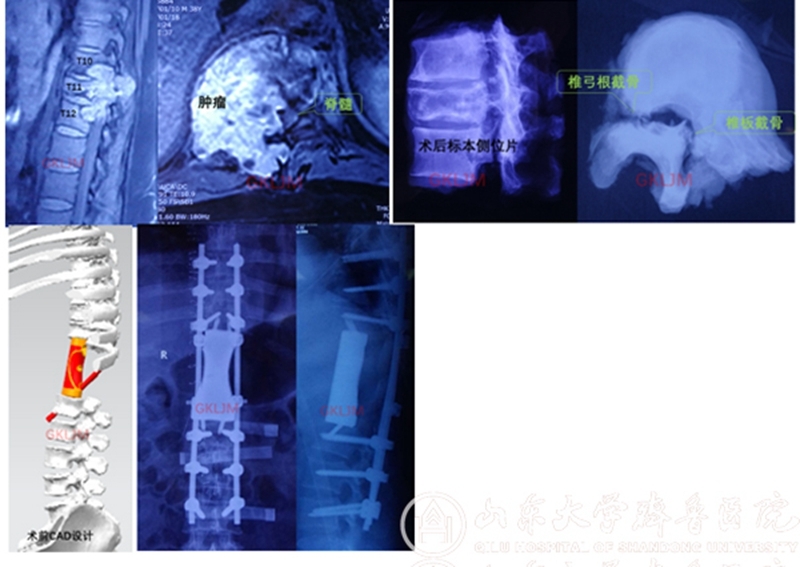

该患者因“双下肢疼痛、麻木1个月,无力10余天”来齐鲁医院就诊,之前曾在当地医院行穿刺活检,病理报告为低度恶性脊索瘤,因当地医院无能力切除肿瘤,患者慕名找到齐鲁医院骨肿瘤科李建民主任。当时患者已无法站立,处于截瘫的边缘,检查发现肿瘤累及第10-12三个胸椎,右侧椎旁形成软组织包块并侵犯膈肌,肿瘤侵入椎管压迫脊髓造成截瘫。

患者影像学检查

1月30日,经过充分术前准备后手术开始了,先在病椎上下各置入6枚椎弓根螺钉,切断并部分切除双侧6根肋骨,将脊椎一侧椎弓根打断,另一侧则经椎板截骨以减少肿瘤污染,整块切除后方附件,将三节段椎体绕过脊髓从右侧取出。李建民团队历时14个小时,克服了出血凶猛过万毫升的困难,顺利完成第10-12胸椎三节段切除,3D打印假体精准重建。术后患者恢复顺利,下肢感觉肌力逐渐好转。

3D打印即快速成型技术的一种,它是一种以数字模型文件为基础,运用粉末状金属或塑料等可粘合材料,通过逐层打印的方式来构造物体的技术,目前在各行各业中获得了广泛应用。而其在医学中的应用更是具有得天独厚的优势,常见的CT数据处理后即可得到打印数据,导入3D打印机即可打印出与原型尺寸、形状一致的模型,结合计算机辅助设计(CAD)技术可设计打印导板、内植物,更值得期待的是利用活的细胞作为打印材料直接打印有活性组织和脏器的生物打印技术。

由于骨肿瘤切除范围的不规律性和复杂性,经常面临骨关节缺损重建困难的问题,而3D打印的个体化定制恰恰满足了骨肿瘤切除重建精准、灵活的要求,在我院领导的支持下,借助于上海九院戴克戎院士的技术支持,骨肿瘤科积极开展了3D打印技术的临床转化应用,不但打印模型、导板,还设计打印金属内植物,已应用于脊柱、骶骨、骨盆、四肢等肿瘤切除后的重建,取得了良好的效果。